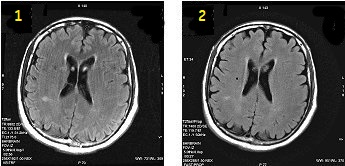

PROPELLER T2 FLAIR scan

PROPELLER with T2 FLAIR can significantly reduce patient motion artifact due to the oversampling of k-space center. The oversampling allows for checking raw data inconsistencies and performing motion correction to the reconstruction process. PROPELLER T2 FLAIR imaging provides robust T2-weighted imaging with CSF suppression. When CSF is suppressed, you get better visualization of gray and white matter.

PROPELLER T2 FLAIR reduces patient motion artifact compared to traditional T2 FLAIR with comparable scan time.

| 1 | FLAIR 2:56 |

| 2 | PROPELLER T2 FLAIR 3:27 |